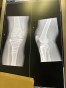

Today, my surgeon and I reached a consensus on what needs to happen going forward concerning my leg. I need to have surgery again to remove the steel appliance and the screws in my right leg. He wants me to have the surgery in the fall, as this gives me the best prognosis and outcome. I agree.

The plan is to have the surgery in November, and it is hoped that once I have completed a period of rehabilitation, my leg may be more normal. The nerve damage I have suffered is appreciable, and that will not restore, and likely get worse, however the functionality of my leg should improve over time, which is essentially what I’m looking for. Less swelling, less pain.